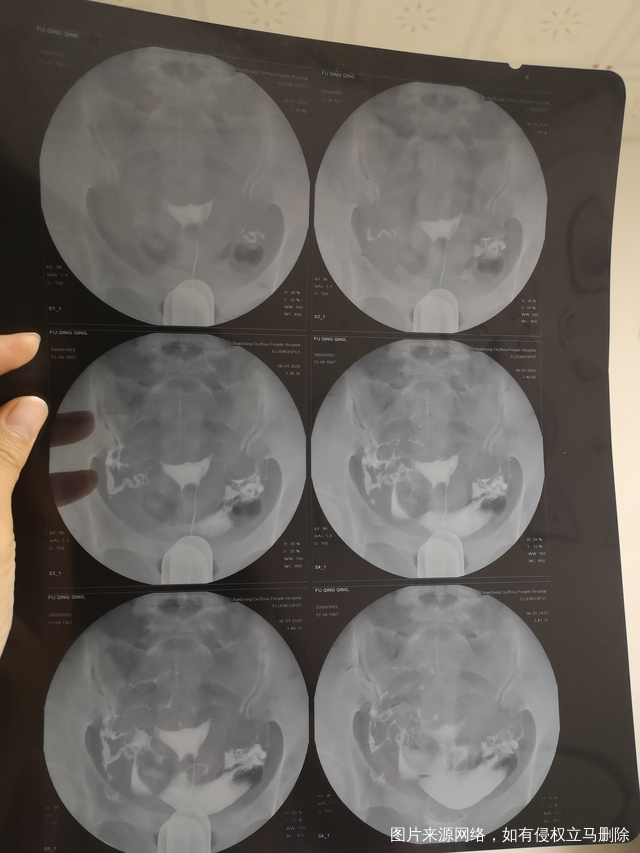

卵巢功能下降这是输卵管造影麻烦看一下

做完输卵管造影第六天了小腹还是感觉沉甸甸的如

可以热敷腹部,如果有发热,腹痛加剧,白带量多,有异味,随时就医